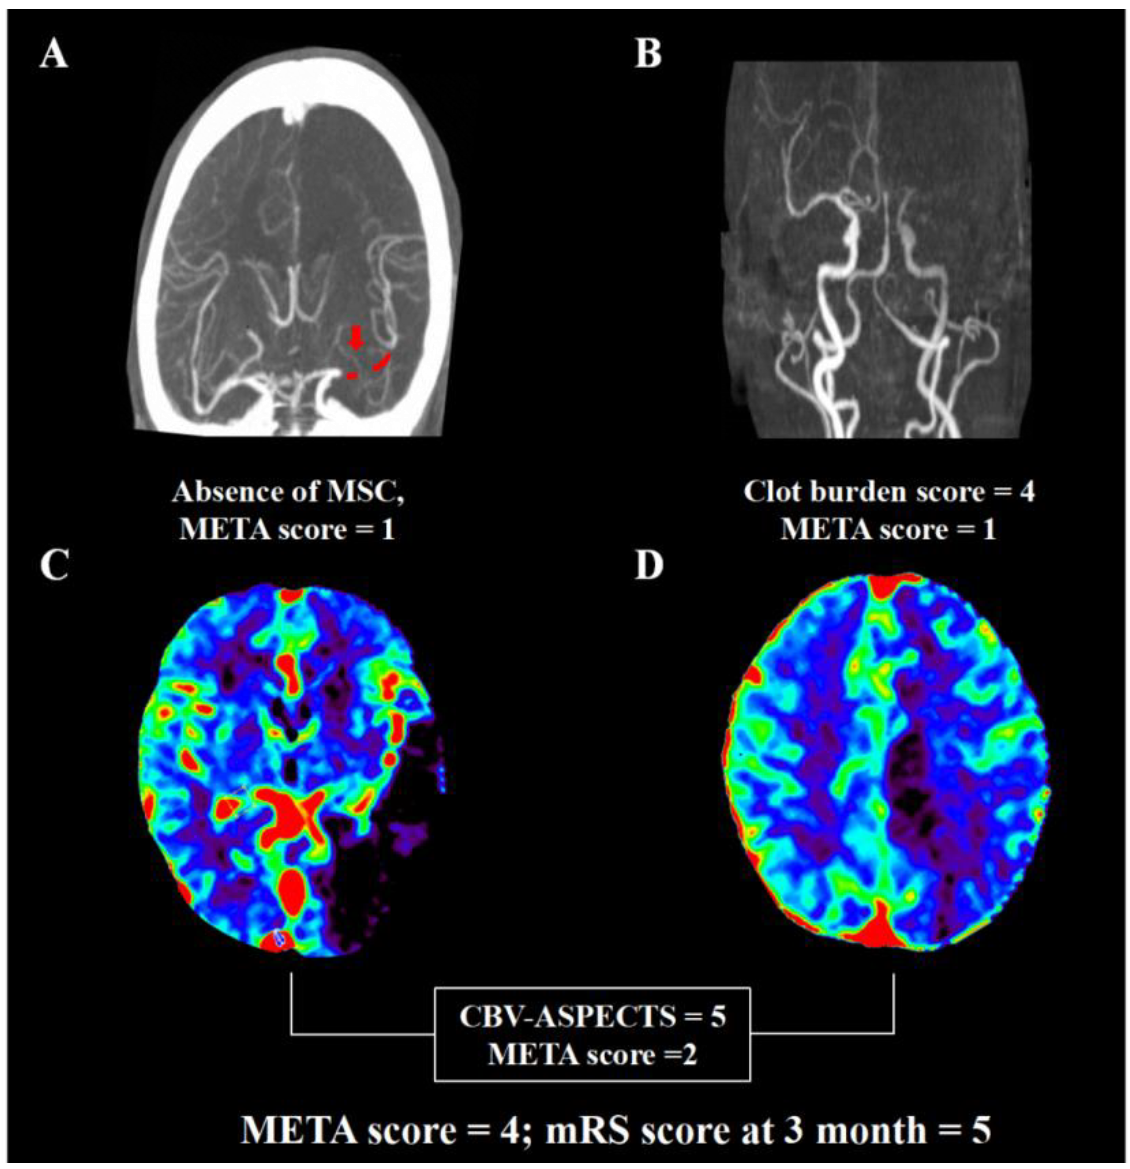

The AUC of the META score was higher than other previously established prediction scales including the PRE score, THRIVE score, and any single component in the META score (Figure 1). The risk of poor outcome increased with a higher META score (0 = 35.9%, 1 = 47.9%, 2 = 60.0%, 3 = 73.3%, 4 = 80.6%, and 5 = 100%; p < 0.001). Representative images of multi-mode imaging in META are shown in Figure 2.

Figure 2.

Representative images for calculation of META. A male patient had occlusion of left middle cerebral artery on dynamic computed tomography angiography (A,B). He had clot burden score of 4 (occlusion of M1 and M2), one segment of clot (red dot that the red arrow points to, (A)), good collateral with >50% filling of the occluded middle cerebral artery territory (A). Cerebral blood volume map (C,D) demonstrated the Alberta Stroke Program early CT score of 5. Thus, the META score was 4. The modified Rankin score was 5 at 3 months despite successful recanalization.